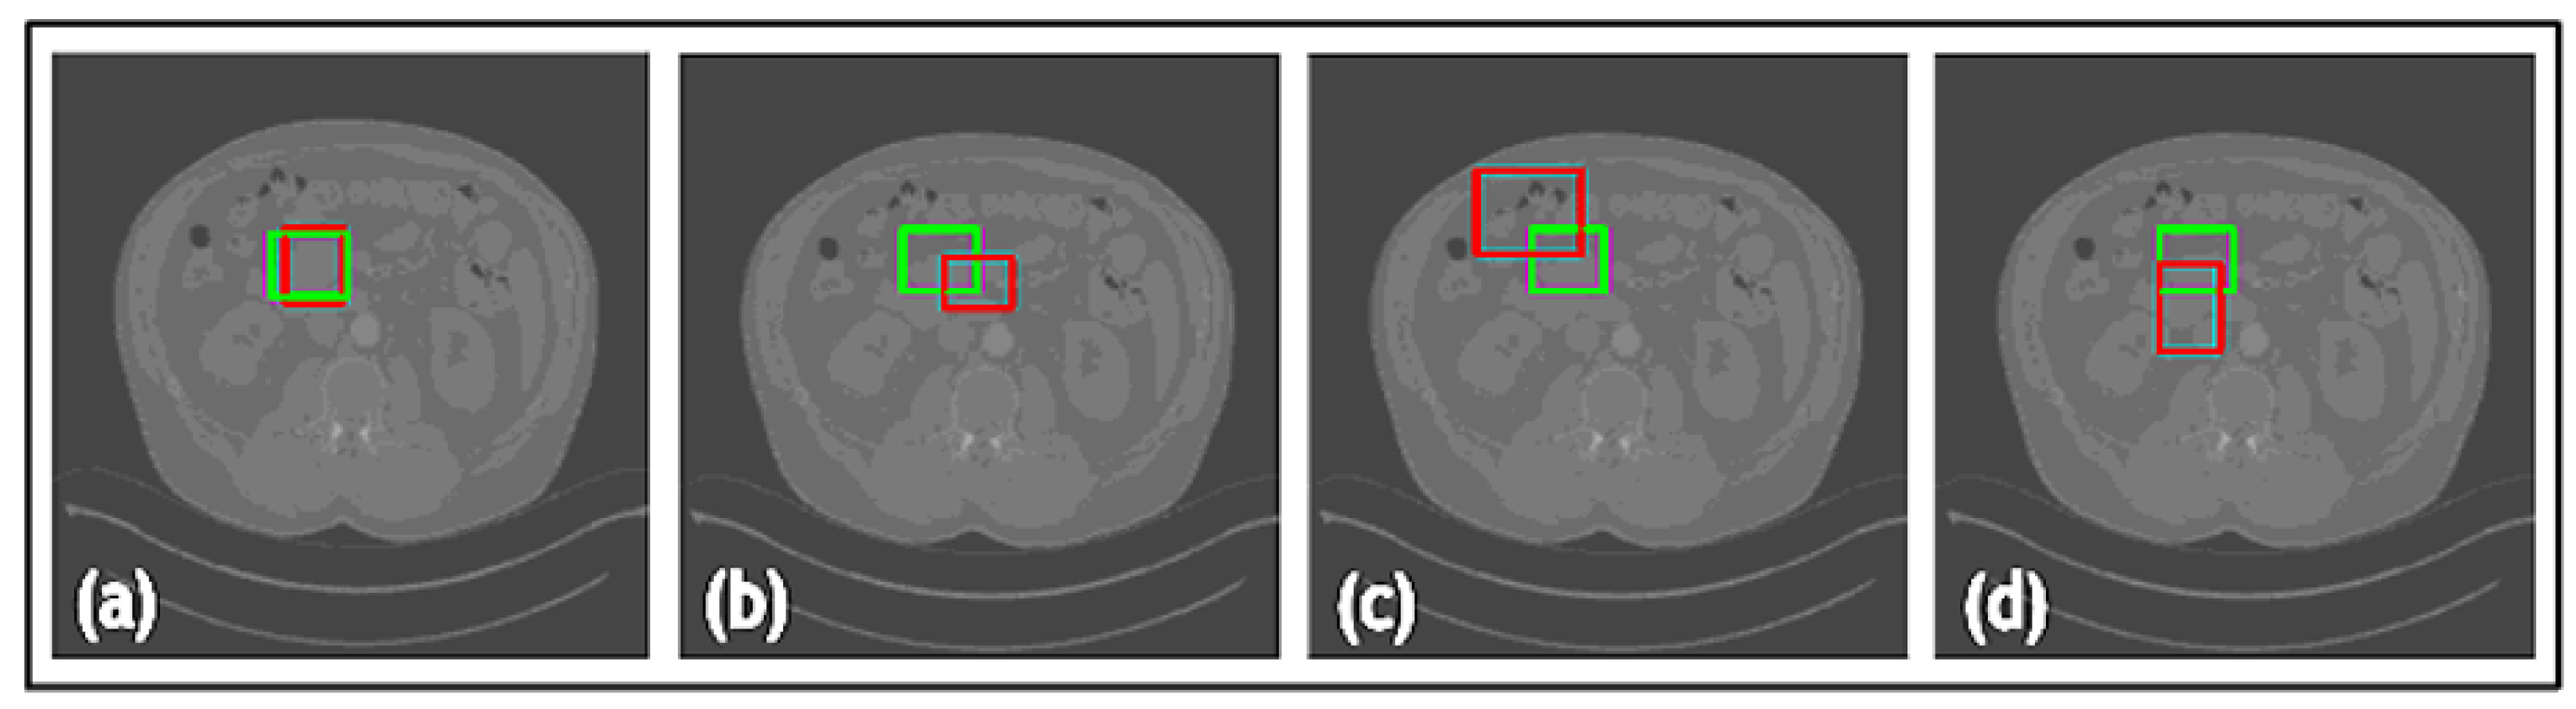

- A novel TED framework is developed, focusing on detecting relevant lesions in noisy OCT images of different organs.

- In TED, the transformer is adapted to take in images and slide across Regions of Interest (ROIs) provided by AGs. This design aims to adaptively deal with different types of noise artifacts and thus effectively detect a variety of anomalies including tooth decay and numerous lesions across two modalities.

- A new loss function is proposed along with TED, which combines a sliding box, Intersection Over Union (IOU), and Mean Squared Error (MSE). It compares the IOU and MSE between the predicted and real bounding boxes to evaluate the regions of focus chosen by the AGs.